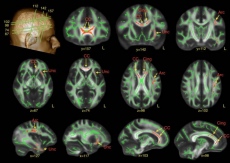

Investigadores de la Universidad de Cantabria, del Instituto de Investigación Valdecilla (IDIVAL), del Centro de Investigación Biomédica en Red de Salud Mental (CIBERSAM), dependiente del Instituto de Salud Carlos III, y del Hospital Universitario Marqués de Valdecilla, en España, han participado en un estudio que no ha encontrado asociación entre las variantes comunes implicadas en la esquizofrenia y el volumen de las áreas subcorticales cerebrales.

Estudios genéticos previos de estudios de asociación pangenómica (GWAS en sus siglas en inglés) sugieren que las alteraciones presentes en los genes de las personas que padecen la enfermedad se caracterizan por la existencia de un número de variaciones comunes que cuando se producen de manera conjunta se asocian a la aparición de la esquizofrenia. Por otra parte, investigaciones anteriores en neuroimagen han encontrado que ciertas estructuras cerebrales presentan anomalías en los pacientes que padecen esquizofrenia.

“En este trabajo, integramos resultados de variantes genéticas implicadas en la esquizofrenia y volúmenes de estructuras subcorticales cerebrales. No encontramos asociación entre el riesgo genético y el volumen de las áreas subcorticales”, explica el Dr. Sullivan.

Para el Dr. Crespo Facorro, “este tipo de trabajos, con datos de más de 43.000 sujetos sanos y 33.000 pacientes, solo son posibles a través de consorcios internaciones tales como el Psychiatric Genomics Consortium (PGC) y ENIGMA (Enhnacing NeuroImaging Genetics through Meta-Analysis)”.